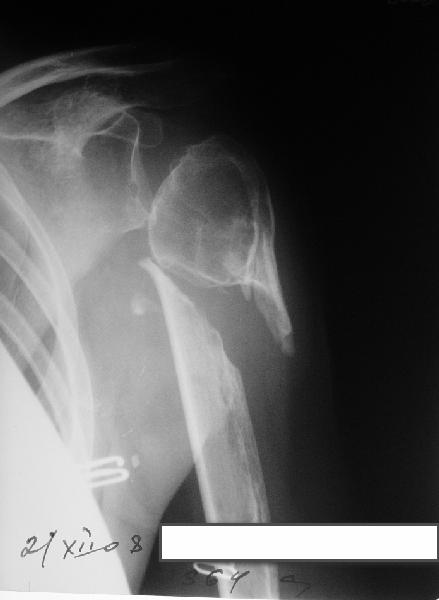

[Ortho] Несращение плеча, деформация головки

Больная 40 лет, множественная травма в июне 2007 года. Лечилась в городской больнице.

Повреждение проксимального отдела плеча вели  консервативно в гипсовой

повязке. В настоящее время больную беспокоят боли в области плечевого

сустава, слабость верхней конечности. Амплитуда движений в плечевом

суставе в пределах 30-40 градусов. Пациентка хотела бы увеличить объем

движений и силу.

Движения сейчас в основном за счет ложного сустава. Варианты -

остеосинтез, артролиз, эндопротезирование, оставить как есть. Как-то

ни один однозначно не привлекает.